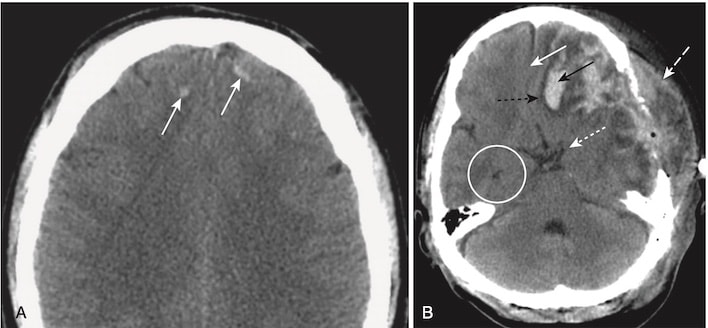

| Thoát vị dưới liềm (Subfalcine herniation) | Não trên lều, cùng với não thất bên và vách trong suốt, thoát vị bên dưới liềm não và dịch chuyển qua đường giữa sang bên đối diện (xem Hình 12, A). |

| Thoát vị xuyên lều (Transtentorial herniation) | Thường thì các bán cầu đại não bị dịch chuyển xuống dưới qua khuyết (incisura) dưới lều, chèn ép sừng thái dương cùng bên và làm giãn sừng thái dương đối bên (xem Hình 12, B). |

| Thoát vị lỗ lớn/hạnh nhân (Foramen magnum/ tonsillar herniation) | Não dưới lều bị dịch chuyển xuống dưới qua lỗ lớn. |

| Thoát vị xương bướm (Sphenoid herniation) | Não trên lều trượt qua xương bướm hoặc là ra trước (trong trường hợp của thùy thái dương) hoặc ra phía sau (đối với thùy trán). |

| Thoát vị ngoài sọ | Sự dịch chuyển não qua một khiếm khuyết của xương sọ. |